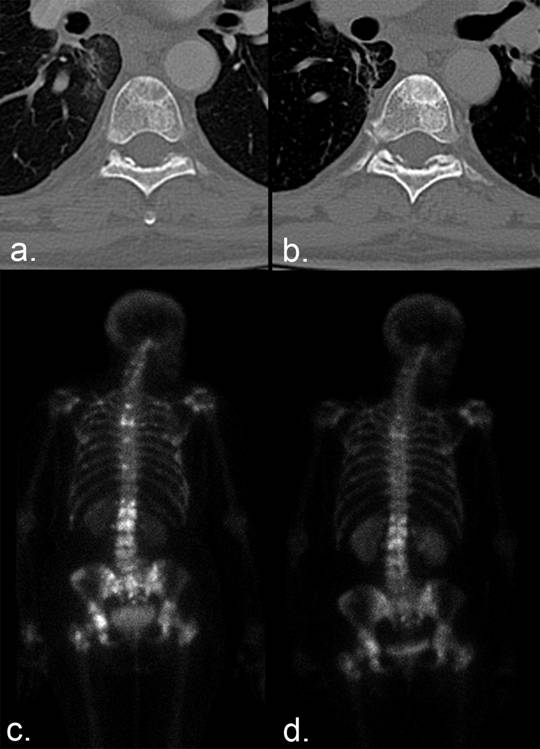

Figure 9

Scintigraphic flare. (a) Numerous bone metastases show tracer uptake on a Tc 99m MDP bone scan in a patient with breast cancer. (b) Companion CT examination demonstrates a lytic metastasis in the L1 vertebral body. (c) Six months later, the lesions demonstrate increased tracer uptake. (d) Companion CT shows sclerotic fill-in of the lytic lesion, which can occur with disease progression or healing. (e, f) Fat-saturated T1-weighted sagittal MRI examinations of the lumbar spine obtained (e) 1 month and (f) 2 months after the bone scans show a decrease in the size and/or enhancement of the metastases, indicating a positive response to therapy. Incidental note is made of interval insufficiency fracture of the superior endplate of L4 on (f). The increased MDP uptake on the bone scan (b) was the result of healing sclerosis and representative of a scintigraphic flare in a patient undergoing partial response rather than progressive disease.